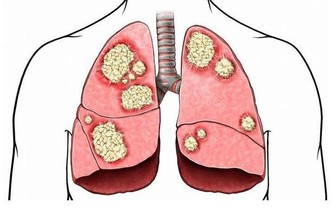

醫學資料顯示,約10%左右的過敏性鼻炎患兒,有可能發展為哮喘患者;

而患哮喘的孩子中,同時患有鼻炎是個很常見的問題。